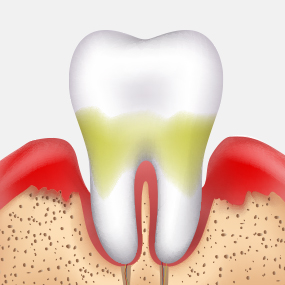

치은염

치주낭 길이 3~5mm 이하

치근활택술 치료